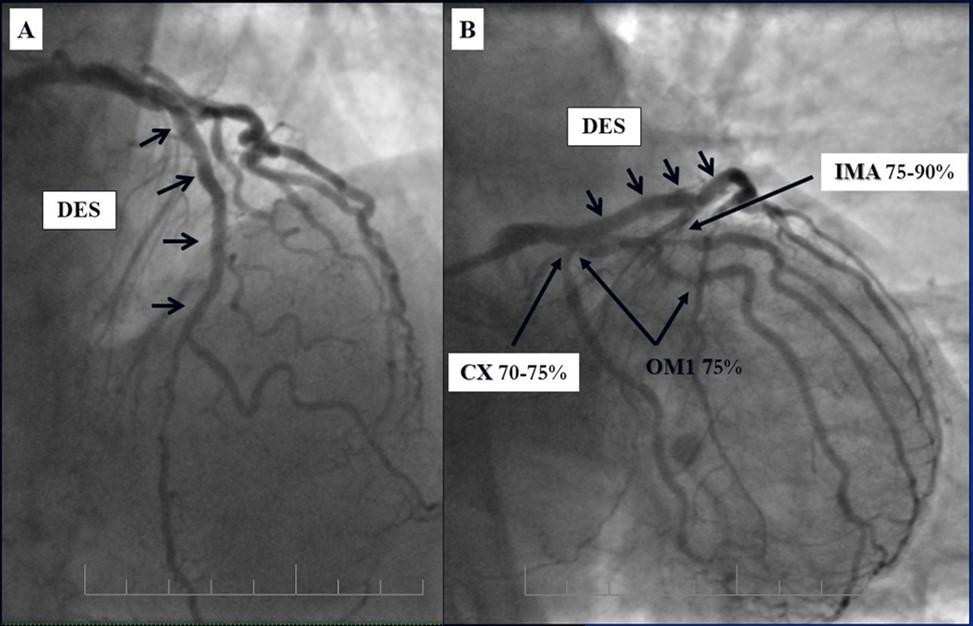

Angiography revealed rare anatomical variation LMCA quadrifurcation (Figure 1, Figure 2), 50% stenosis of the distal part of the LMCA, 40% stenosis of the ostial segment of left anterior descending (LAD) artery and diffuse prolonged 70-75-95% stenosis in mid-segment (Figure 3), 75% stenosis of the ostial segment of the circumflex (CX) artery, 75% stenosis of the ostial segment of the first marginal branch (OM1), 75-90% stenosis of the proximal segment of the intermediate artery (IMA), prolonged diffuse severe 90-95% stenosis of mid-segment of the right coronary artery (RCA) (Figure 4).

Figure 3.Prolonged diffuse severe 90-95% stenosis of mid-segment of the right coronary artery. A - Left anterior oblique 45° projection; B – Right anterior oblique 45° projection.

Figure 4.A - 50% stenosis of the distal segment of the LMCA; B - 70-75-95% stenosis in mid-segment of the LAD.